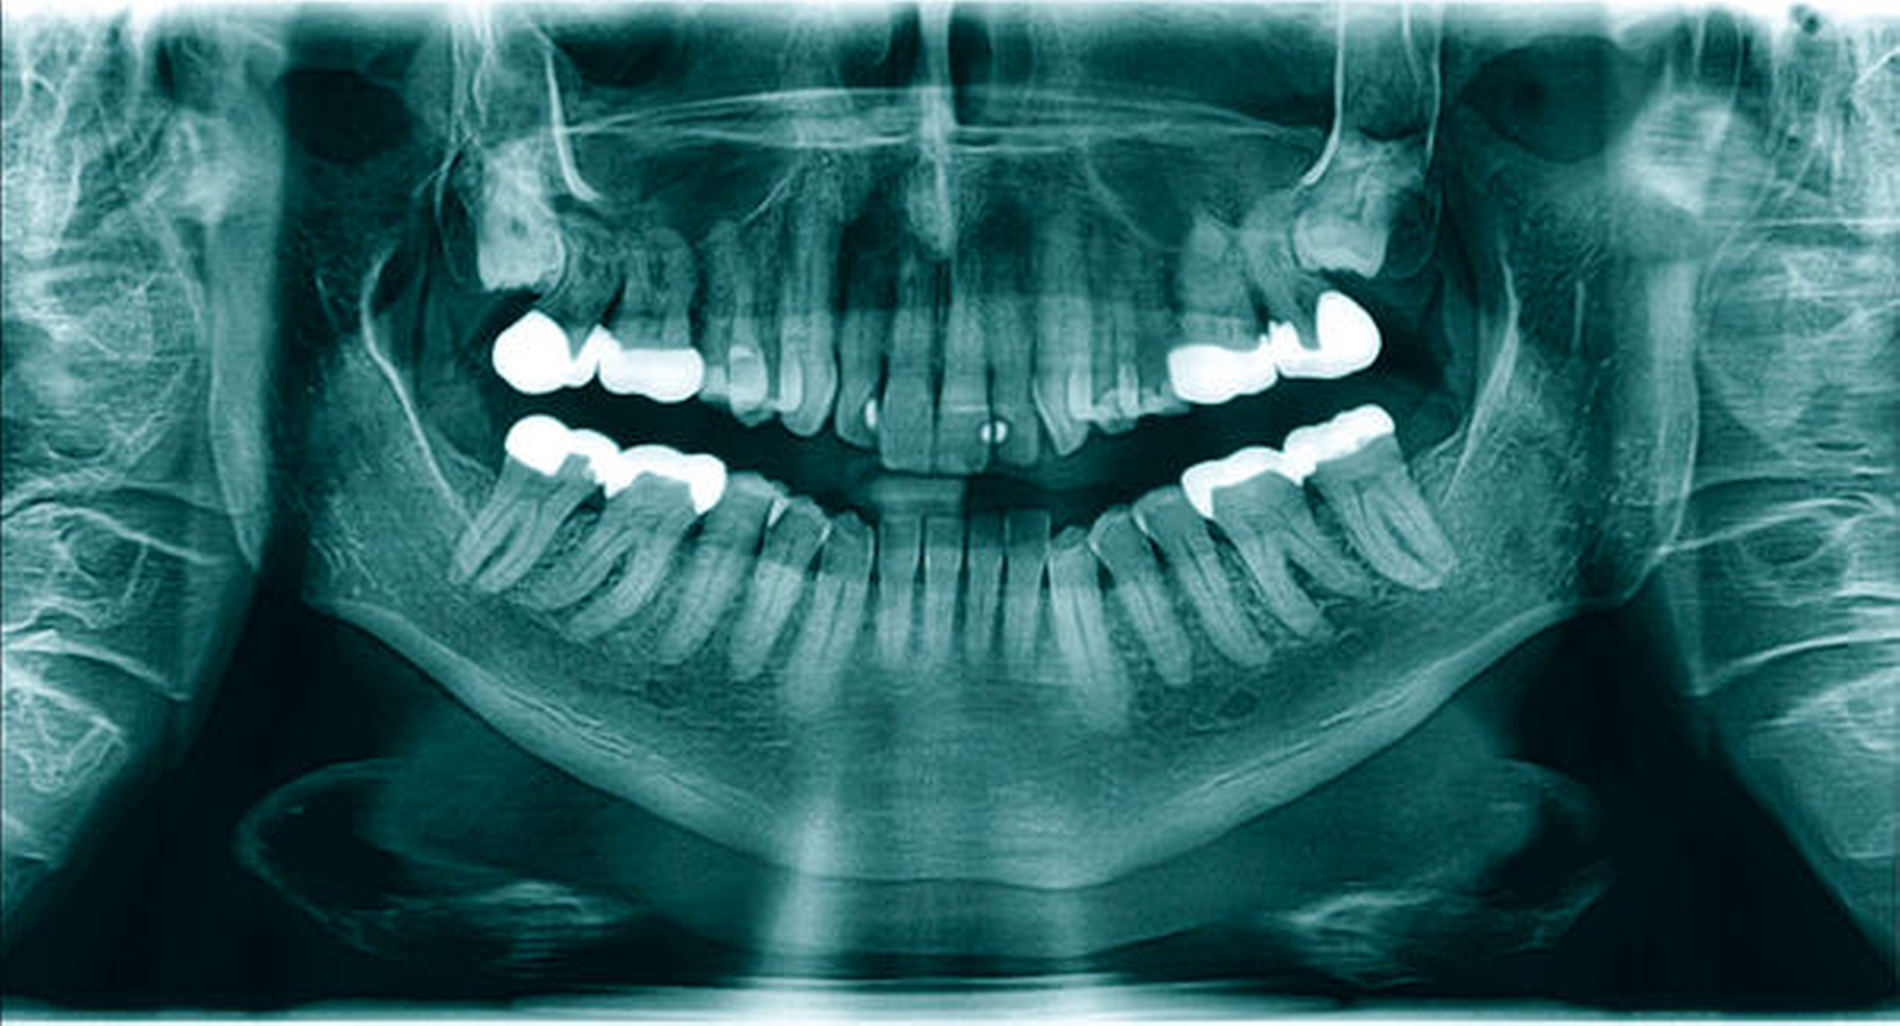

Nebenbefundlich zeigte sich in der PSA (Abbildung 1) im Bereich des rechten Kieferastes eine circa 10 mm x 6 mm große, klar begrenzte, knochendichte Opazität. Diese Opazität erschien als am Rand opak verdichtete und nicht infiltrierende Struktur, die mit keiner erkennbaren dentogenen oder nicht-dentogenen Struktur direkt korrelierte. Auf einer zum Vergleich vom Hauszahnarzt angeforderten PSA, die etwa neun Jahre zuvor erstellt wurde, ist ein vergleichbarer Befund zu sehen (Abbildung 2).

Zu erkennen waren im rahmenartig flankierenden Abschnitt des reifen Knochengewebes enthaltene Fettzellnester. Die äußere Begrenzung erschien undulierend, aber scharfkantig. Bestätigt wurde zudem die vollständige Exstirpation der Läsion. Die Histologie ergab eine Gewebsaussprengung atypiefreien Knochengewebes, das am ehesten mit einem ossären Choristom zu vereinbaren ist. Da Rezidive bei Choristomen nicht zu erwarten sind, erfolgte nach Nahtentfernung und Erstellung einer post-operativen PSA (Abbildung 4) keine Nachkontrolle mehr bei uns.